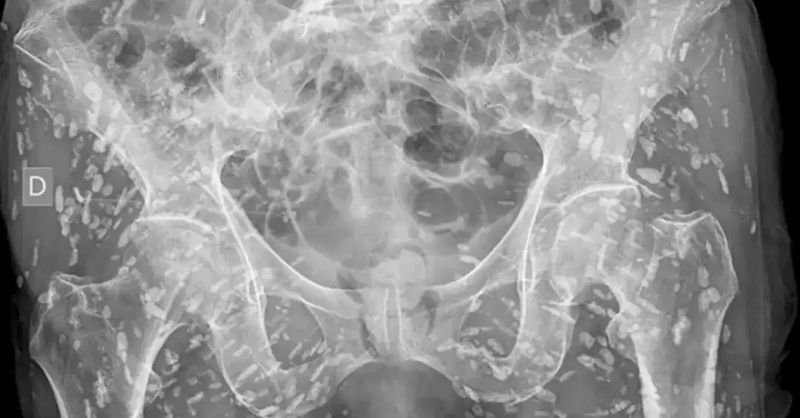

ℍ𝕠𝕣𝕣𝕚𝕗𝕚𝕔 x-ray shows parasites embedded into human skin after someone made major mistake

An X-ray image has been making waves online this week, revealing the unsettling reality of what a parasite looks like when it burrows into human soft tissue. Let’s...